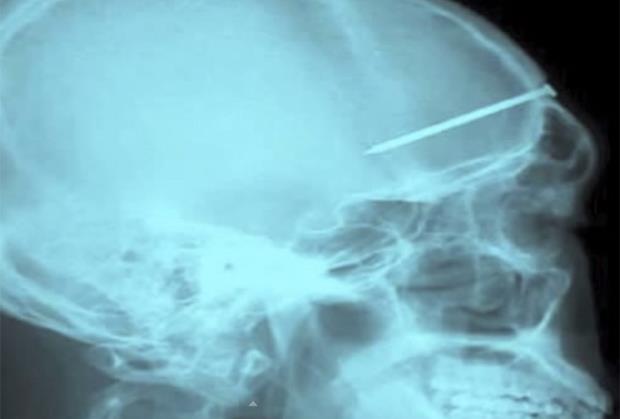

LUDOSTI: 25 najčudnijih stvari koje je rendgen snimio u ljudskom telu